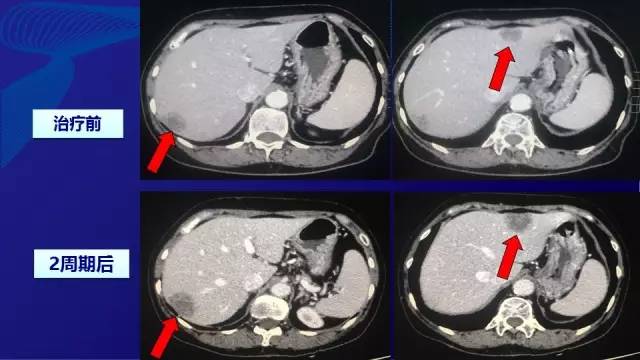

● 2015-3月 二线治疗:伊立替康+替吉奥 –伊立替康:180 mg/m2,d1 –替吉奥: 40mg,bid,d1-d14 ——每3周一周期,无不可耐受不良反应

● 2周期后评效:PD